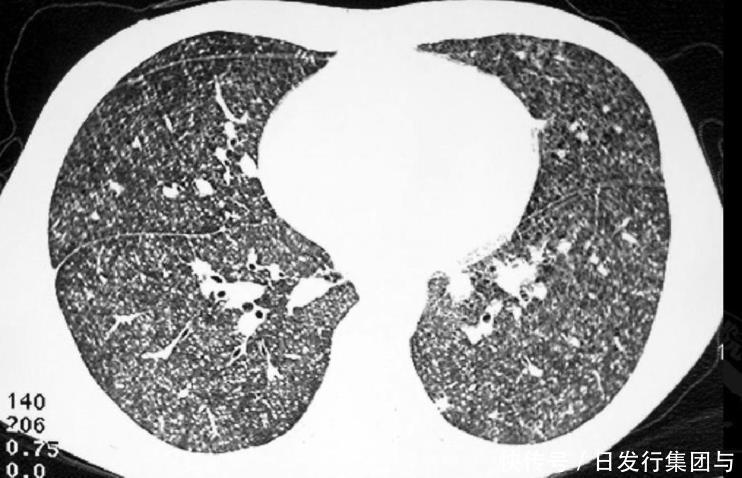

俗话说三十而立、四十知天命,但是40之后的人们也更容易被各种肺病所缠身困扰,而肺结节病情一旦控制不当,还有一定几率恶化成癌,所以平时更应引起足够重视。

其实对于肺结节的发作,也并不是一蹴而就的,很多情况下都是因为受到内外界不利因素的刺激,而逐渐诱发。临床上对于这类病情的治疗方式包括:手术切除、对症用药、随访复诊等方式。

并不是所有的结节都要动辄手术,对于一些直径在1.8cm以下的结节,如果没有毛刺、内部钙化、外周血流丰富等恶化态势,可以坚持随访复诊的方式。只要结节病情没有变化,就不需要采取任何处理方法,保守调理即可。